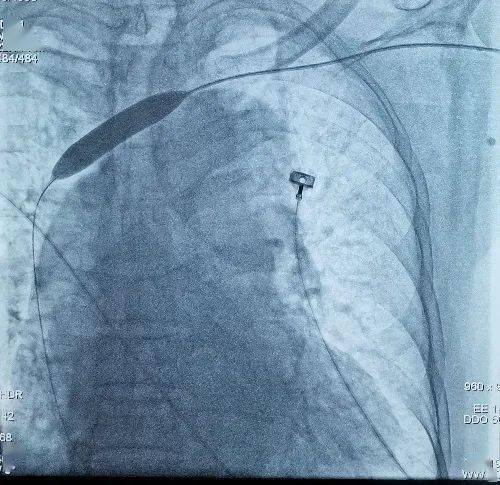

球囊扩张狭窄的左侧无名静脉

手术中 , 张煜程通过DSA下静脉造影 , 评估老人静脉狭窄的位置及狭窄程度 , 发现老人的左侧无名静脉出现狭窄 。

随后 , 他通过球囊扩张 , 缓慢谨慎地扩张了狭窄的血管 , 之前通行受阻的静脉血得以畅通进入心脏 , 成功疏通老人的“生命线” 。